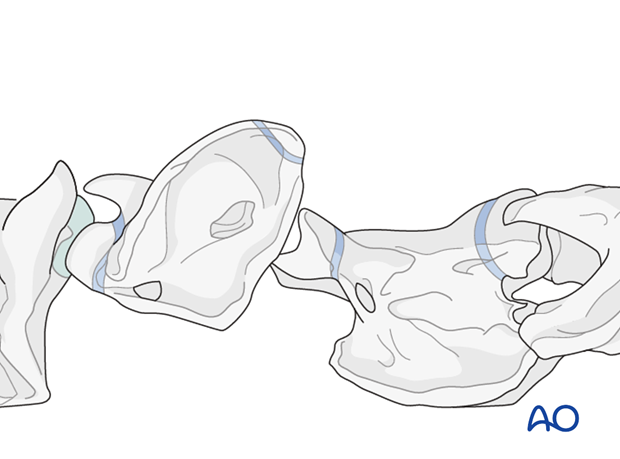

Complete luxation of the atlantoaxial articulation, resulting in displacement of the dens so that it lies ventral to the atlas, is very rare. For a complete luxation to develop there needs to be complete disruption of the ligamentous attachments of the dens. Complete luxations are treated nonsurgically.

Subluxation of the atlantoaxial articulation, without fracture of the dens, is a rare condition seen in young horses up to 3 years of age. The condition can be congenital in origin or the result of a traumatic incident. Plates are used to perform arthrodesis of C1-C2 as treatment for subluxations.

On plain radiographs, there is malalignment of the atlas and axis.